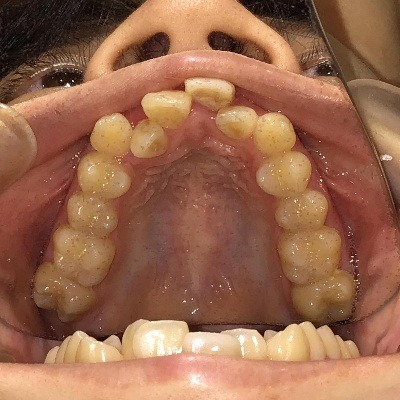

上顎

| 治療詳細 | 叢生や交叉咬合を整えるために、歯の表面にアタッチメント(白い突起)をつけ、IPR(歯と歯の間を削る)を行いました。 また、顎間ゴムと呼ばれる引っ掛けるゴムの補助装置も用いて治療を行いました。 抜歯を1本して治療を行いました。該当部分は義歯を使用しています。 |

| 主訴 | 歯のがたつき 一部分だけかみ合わせが反対 |